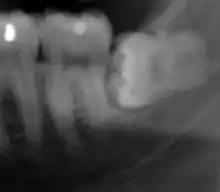

For partially impacted teeth in those over 20 year of age, the most common pathology seen, and the most common reason for wisdom teeth removal, is pericoronitis or infection of the gum tissue over the impacted tooth. The bacteria associated with infections include Peptostreptococcus, Fusobacterium, and Bacteroides bacteria. The next most common pathology seen is cavities or tooth decay. Fifteen percent of people with retained wisdom teeth exposed to the mouth have cavities on the wisdom tooth or adjacent second molar due to a wisdom tooth. The rate of cavities on the back of the second molar has been reported anywhere from 1% to 19% with the wide variation attributed to increased age.[12]

In five percent of cases, advanced periodontitis or gum inflammation between the second and third molars precipitates the removal of wisdom teeth.[5]: 141 [6] Among patients with retained, asymptomatic wisdom teeth, roughly 25% have gum infections (periodontal disease).[13]: ch13 Teeth with periodontal pockets of greater than 5mm have tooth loss rates that start at 10 teeth lost per 1000 teeth per year at 5mm to a rate of 70 teeth lost per year per 1000 teeth at 11mm.[14]: 57 The risk of periodontal disease and caries on third molars increases with age with a small minority (less than 2%) of adults age 65 years or older maintaining the teeth without caries or periodontal disease and 13% maintaining unimpacted wisdom teeth without caries or periodontal disease.[15] Periodontal probing depths increase over time to greater than 4 mm in a significant proportion of young adults with retained impacted wisdom teeth which is associated with increases in serum inflammatory markers such as interleukin-6, soluble intracellular adhesion molecule-1 and C-reactive protein.[16]